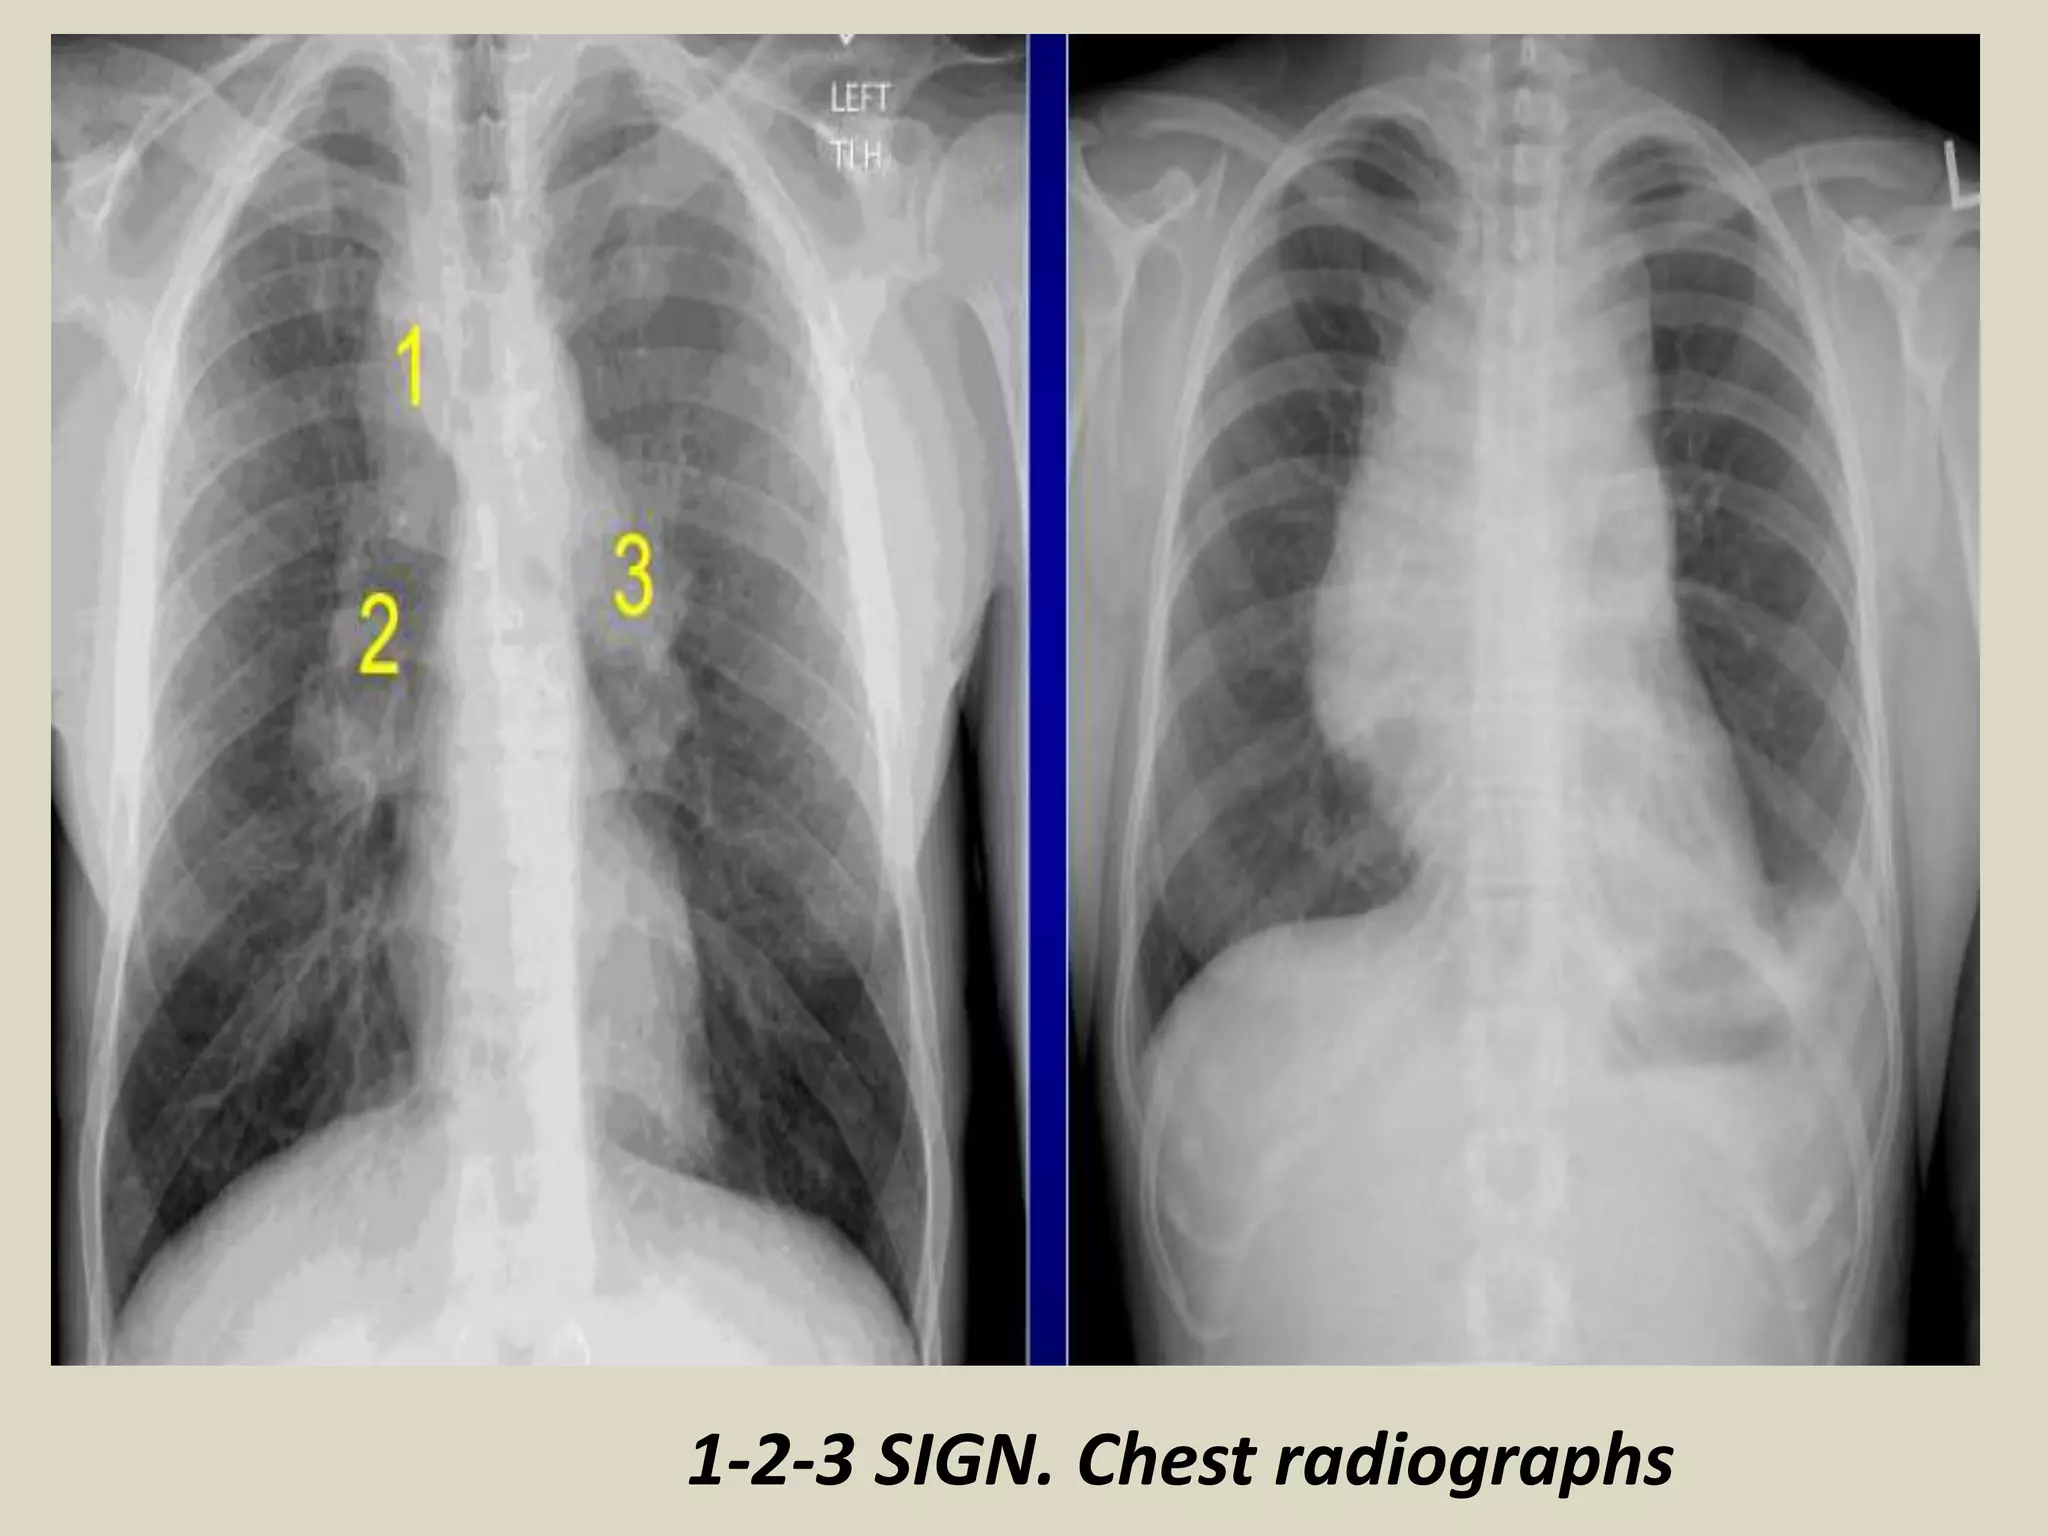

1-2-3 SIGN

Characterized by bilateral hilar and right paratracheal lymphadenopathy so-called

Garland triad or 1-2-3 sign

Suggestive of sarcoidosis

Separation between nodes and heart which is not seen in lymphoma

1-2-3 SIGN. Chest radiographs with schematic drawings. Sarcoidosis.

1-2-3 SIGN. Chest radiographs